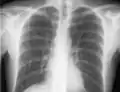

Luego, la línea se inserta usando la técnica de Seldinger: se pasa una guía roma a través de la aguja y luego se retira la aguja. Se puede introducir un dispositivo de dilatación sobre el alambre guía para aumentar el diámetro. Finalmente, la propia línea central se pasa por encima del alambre guía, que luego se retira. Se aspiran todos los lúmenes de la vía (para asegurarse de que estén colocados dentro de la vena) y se lavan con solución salina o heparina.[1] Posteriormente, se puede realizar una radiografía de tórax para confirmar que la vía está colocada dentro de la vena cava superior y que no se causó neumotórax accidentalmente. En radiografías anteroposteriores, una punta de catéter entre 55 y 29 mm por debajo del nivel de la carina se considera una ubicación aceptable.[33] El seguimiento electromagnético se puede utilizar para verificar la ubicación de la punta y proporcionar una guía durante la inserción, evitando la necesidad de rayos X posteriormente.

Radiografía de tórax con catéter en vena subclavia derecha Radiografía de tórax con catéter en vena subclavia derecha

El contorno de la vena cava superior en una radiografía de tórax está etiquetado a la izquierda. El contorno de la vena cava superior en una radiografía de tórax está etiquetado a la izquierda.